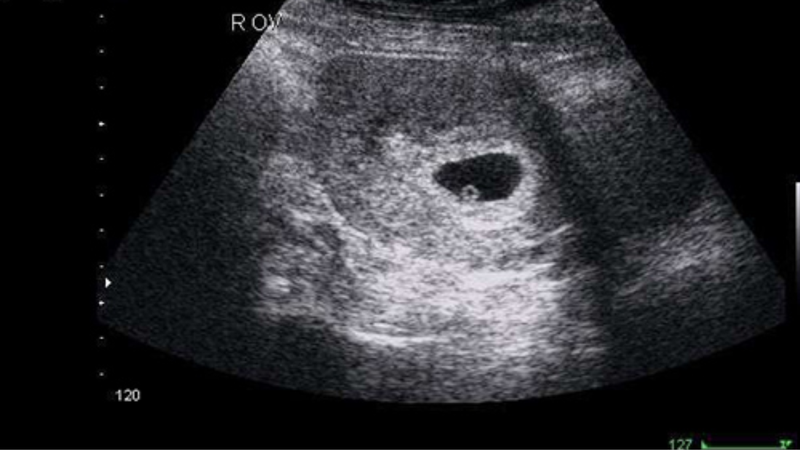

Hình ảnh của thai nhi 5 tuần tuổi vẫn còn rất nhỏ bé. Trong quá trình siêu âm đầu dò, bác sĩ có thể nhận thấy túi thai và túi noãn hoàng nhưng rất hiếm khi quan sát thấy phôi thai, bởi ở giai đoạn này, phôi chỉ hiển thị như những điểm nhỏ bên cạnh túi noãn hoàng. Tùy thuộc vào hình thức siêu âm và trang thiết bị, một số bà mẹ có thể thấy các vùng màu đen với vòng tròn nhỏ bên trong, nơi vùng màu đen đại diện cho túi thai, trong khi vòng tròn nhỏ bên trong chính là túi noãn hoàng.

Túi noãn hoàng có vai trò quan trọng trong việc cung cấp dinh dưỡng cho phôi thai cho đến khi nhau thai phát triển hoàn thiện. Thông thường, túi noãn hoàng sẽ dần biến mất từ khoảng tuần thứ 14 đến tuần thứ 20 khi nhau thai đã hoàn tất phát triển. Đây là giai đoạn khởi đầu của sự sống, một dấu hiệu cho thấy thai nhi đang từng bước phát triển và chuẩn bị cho những tháng tiếp theo.

Người cha mẹ sẽ cảm thấy xúc động và hồi hộp khi nhìn thấy hình ảnh đầu tiên của thai nhi qua siêu âm. Những hình ảnh cho thấy một bầu không khí yên bình bên trong, mang đến cảm xúc tích cực cho cả cha lẫn mẹ. Việc thấy được chứng thực cho sự sống đang phát triển này không chỉ làm tăng thêm sự kết nối của cha mẹ với em bé mà còn cung cấp những thông tin cần thiết để họ chăm sóc bản thân trong suốt thời gian thai kỳ.

Khi được bác sĩ giải thích hình ảnh siêu âm, cha mẹ cần hiểu rõ rằng ở tuần thứ 5, sự nhìn thấy chưa hoàn chỉnh. Nếu bác sĩ không chỉ rõ phôi thai, cha mẹ không nên quá lo lắng vì điều này là bình thường trong giai đoạn này. Sự phát triển của phôi thường chưa hiển thị một cách rõ ràng, điều này không phải là dấu hiệu của sự bất thường.